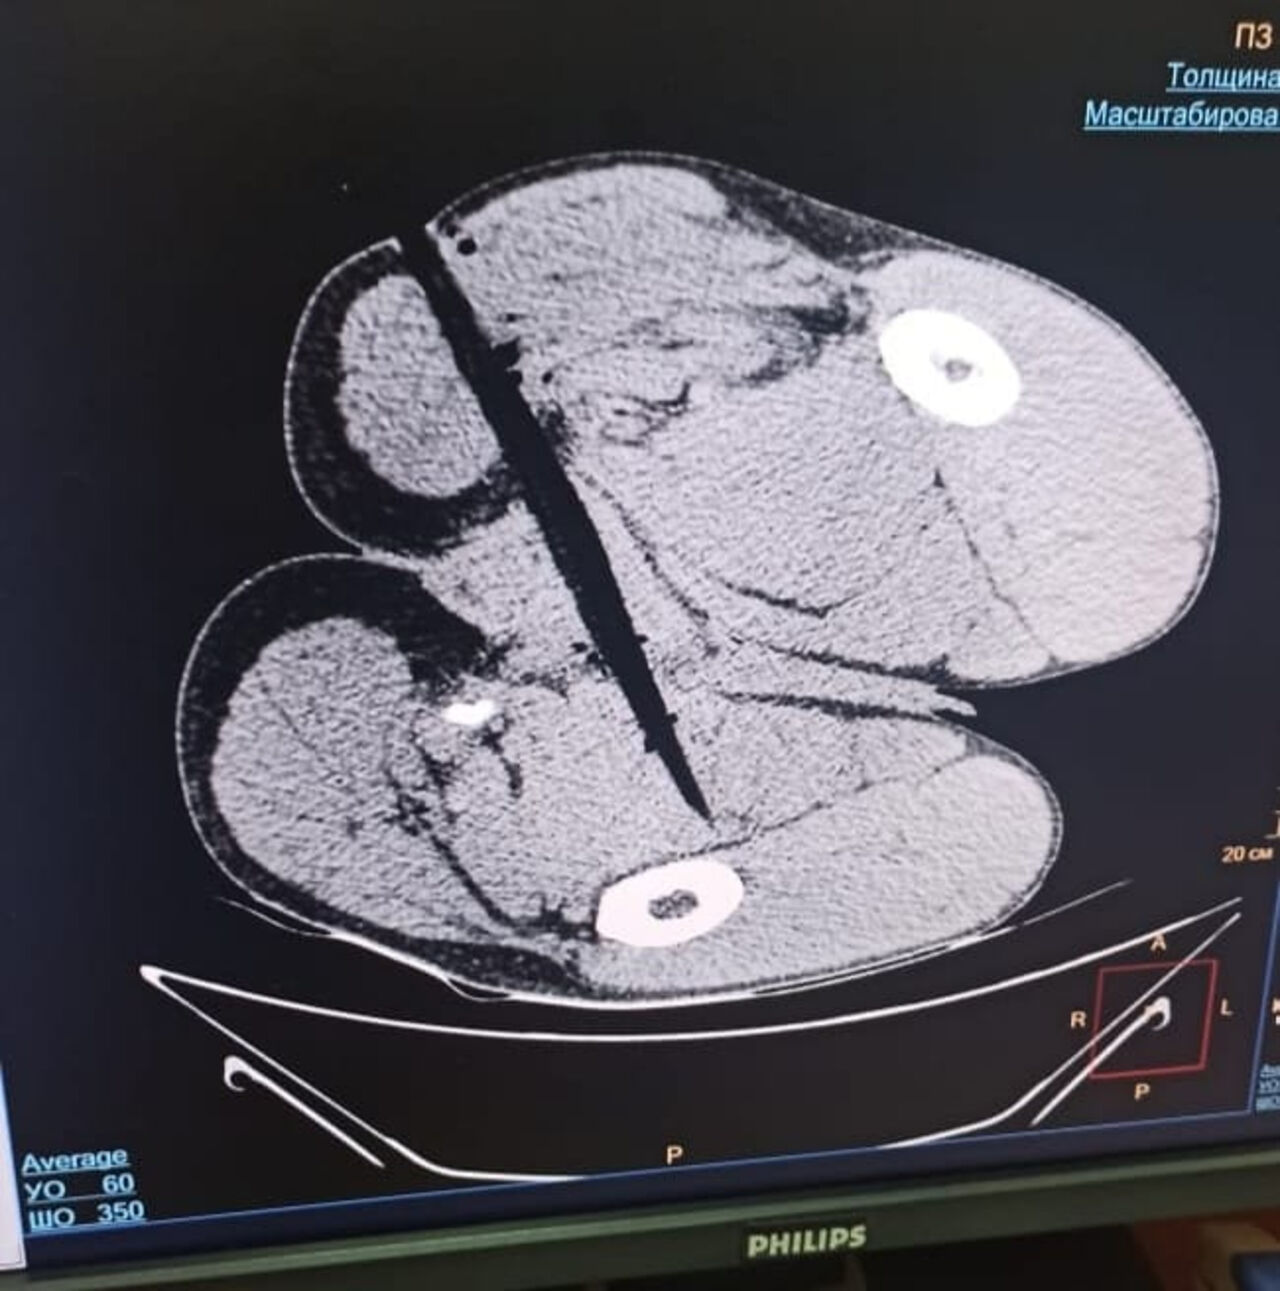

Липецкие врачи вытащили из ягодиц иностранца 40-сантиметровый инородный предмет, пишет издание GOROD48.

Липецкие медики провели необычную операцию пациенту-иностранцу, попавшему в неприятную ситуацию. 41-летний житель Нигерии оказался в руках травматологов после того, как попытался перелезть через забор. Об этом рассказала в своем Telegram-канале министр здравоохранения Липецкой области Анна Маркова.

– Один из майских дней сложился для мужчины крайне неудачно – он пытался перебраться через забор и напоролся на деревянный кол. С инородным предметом в мягких тканях ягодиц и кровотечением пациент был доставлен в БСМП №1, – поделилась глава регионального ведомства.

Медикам удалось остановить кровотечение и достать из раны 40-сантиметровый деревянный кол. Операция прошла успешно.